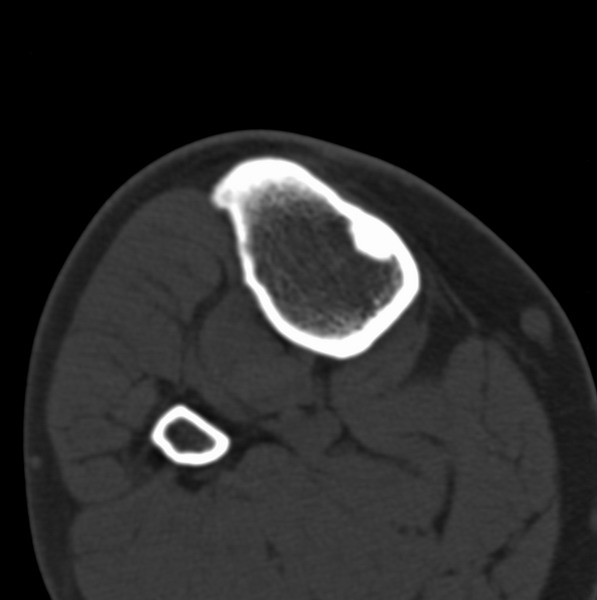

右侧膝关节疼痛一月

男、48

股骨下段、胫骨上段。

1、股骨干骺端病变考虑干骺端纤维性皮质缺损愈后(非骨化性纤维瘤)改变,胫骨近端内生骨瘤(或干骺端纤维性皮质缺损愈后改变);

2、骨关节炎,骨质增生,股骨外侧髁退变性囊肿(关节面软骨下囊肿);

1、股骨干骺端病变考虑干骺端纤维性皮质缺损愈后(非骨化性纤维瘤)改变,胫骨近端内生骨瘤;

支持非骨化性纤维瘤

非骨化性纤维瘤